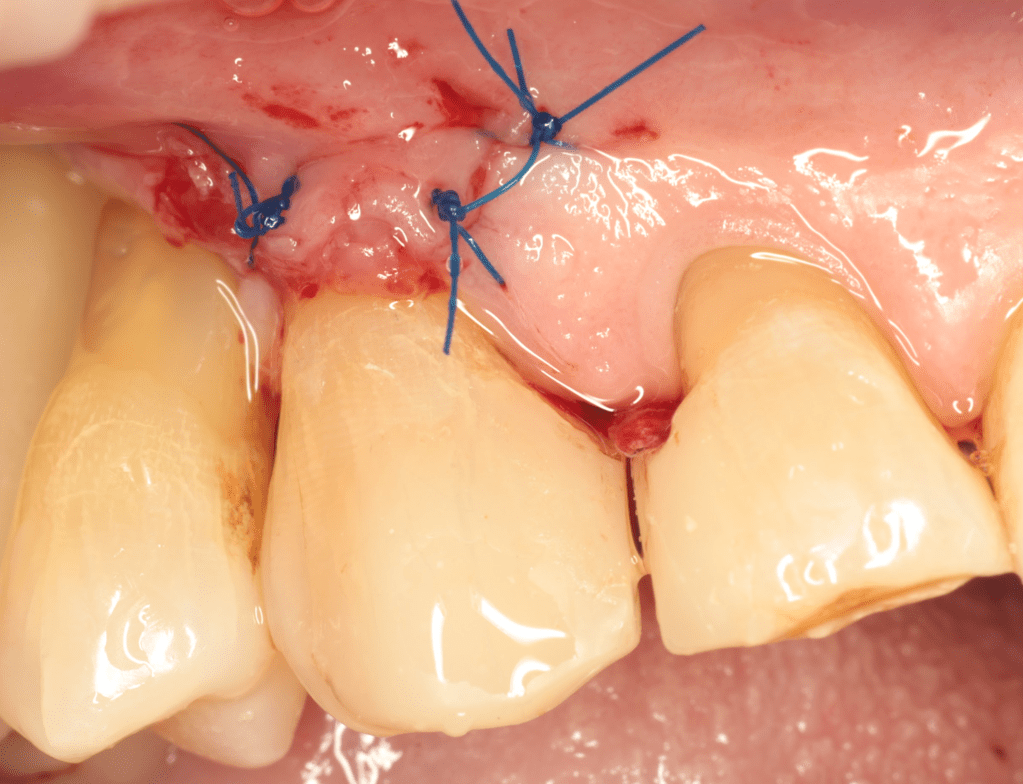

Reconstrucción preendodóntica

Gingivectomía +reco preendo +reconstrucción

Reco preendo + gingivectomía